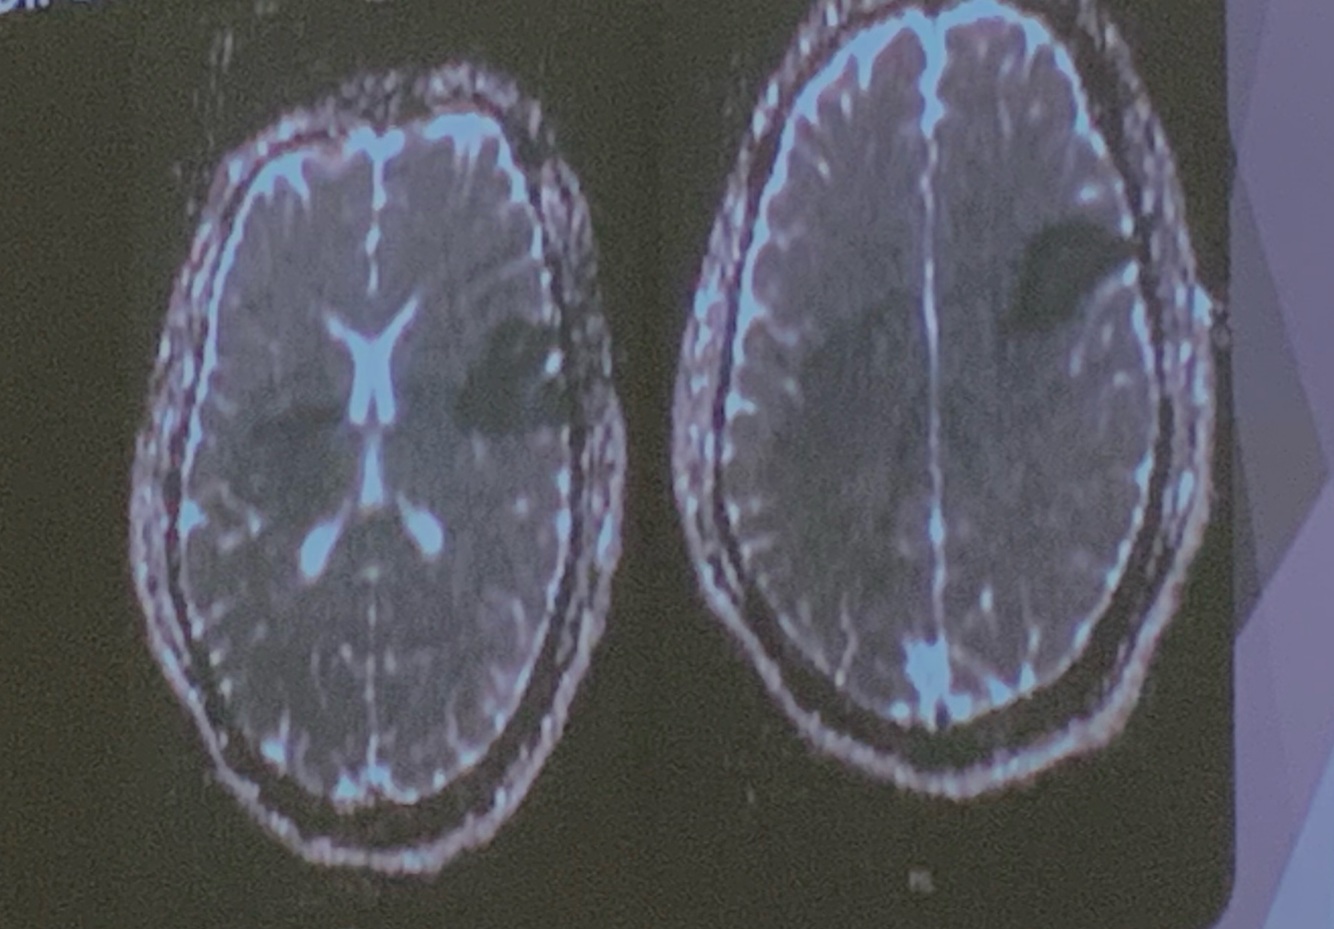

Identifica cual es T1 y T2

T1 izq T2 der